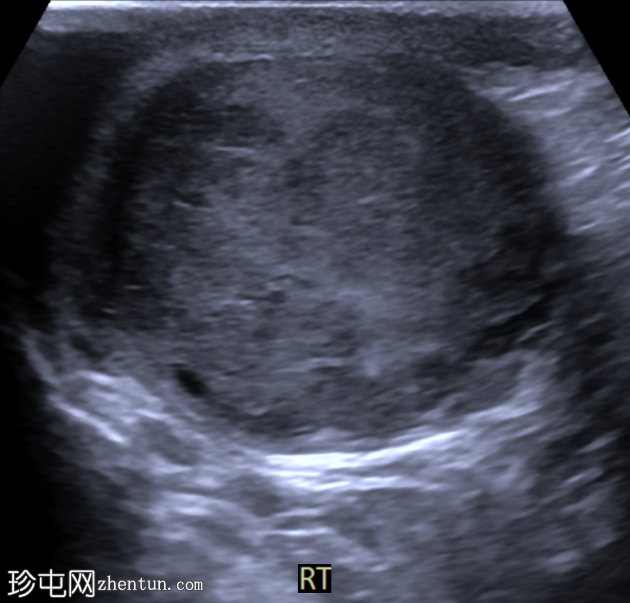

睾丸混合性生殖细胞瘤

右侧睾丸肿块,伴间歇性疼痛4个月。

年龄:30岁

性别:男

超声检查

横切面

右侧睾丸内可见一大小约3.0 x 5.0 cm的异质性分叶状低回声肿块。肿块内未见囊性区域或钙化。彩色多普勒超声检查显示肿块内血流丰富。左侧睾丸正常。